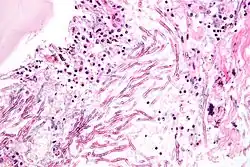

Las micosis (del griego μυκος, hongo) son las infecciones causadas por hongos a animales o vegetales.[1]

Algunas micosis son afecciones oportunistas que prosperan ante una baja de las defensas del sistema inmune del sujeto afectado.[2] Tal baja puede ser causada por estrés, estados psíquicos de ansiedad o depresión, por el retrovirus del VIH-Sida o por ciertos tratamientos quimioterápicos, entre otros factores. Un ejemplo típico de micosis oportunista es la candidiasis.